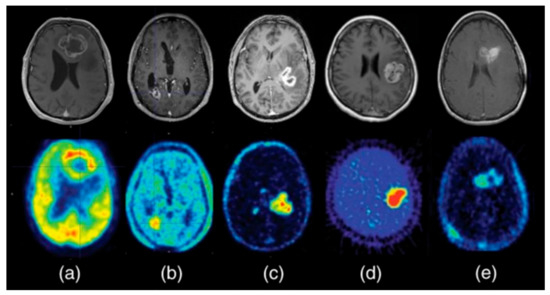

In 2017, a first monoclonal antibody PET imaging study in children was performed in patients with diffuse midline glioma (DMG, formerly known as diffuse intrinsic pontine glioma (DIPG)). The target used for imaging in this study is vascular endothelial growth factor (VEGF) [136]. VEGF is a signaling protein that is located on the cell surface of endothelial cells, which promotes angiogenesis. VEGF can be targeted using the monoclonal antibody bevacizumab (Avastin). Tumor uptake and biodistribution of the drug was visualized by means of PET imaging with [89Zr]Zr-bevacizumab [137]. The results showed that 89Zr-bevacizumab PET imaging is feasible and safe in pediatric patients above 6 years of age. Among seven patients, a marked inter- and intratumoral heterogeneity of 89Zr-bevacizumab uptake was observed, suggesting considerable variability in the tumor delivery of bevacizumab in DIPG patients, which was possibly related to the heterogeneous expression of VEGF and/or variable integrity of the BBB (Figure 3) [137].

Figure 3.

MRI and PET-MRI fusion images of patients with diffuse midline glioma (DMG). (A–G) Top row: [89Zr]Zr-bevacizumab PET (144 hrs post-injection) fused with T1-Gadolinium (Gd) weighted MRI per patient; middle row: T1-Gd weighted MRI; lower row: T2-weighted/Fluid-attenuated inversion recovery (FLAIR) MR-images. Five tumors show a variable uptake of [89Zr]Zr-bevacizumab (white arrows), with both PET negative and positive areas within each tumor. Two primary tumors are completely PET negative (C and E), while the T2 weighted images show tumor infiltration in the whole pons of both patients. In the middle row, the red arrows represent the areas of contrast enhancement within the tumor. In four out of five primary tumors, the PET-positive area corresponds with the contrast-enhancing area on MRI of the tumors (A,B,F and G). In C, the tumor shows an MRI contrast-enhancing area, while there is no 89Zr-bevacizumab uptake. Figure D shows a PET-positive tumor, while no Gd-enhancement is observed on MRI. Adapted from [137]. This research was originally published in JNM. Jansen MH, Veldhuijzen van Zanten SEM, van Vuurden DG, Huisman MC, Vugts DJ, Hoekstra OS, et al. Molecular Drug Imaging: (89)Zr-Bevacizumab PET in Children with Diffuse Intrinsic Pontine Glioma. J Nucl Med. 2017;58(5):711-6. © SNMMI.